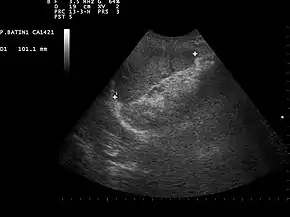

![]() Ultrasound image of a normal spleen that may be seen in part of the eFAST | |

Focused assessment with sonography in trauma (commonly abbreviated as FAST) is a rapid bedside ultrasound examination performed by surgeons, emergency physicians, and paramedics as a screening test for blood around the heart (pericardial effusion) or abdominal organs (hemoperitoneum) after trauma.[1][2] There is also the extended FAST (eFAST) which includes some additional ultrasound views to assess for pneumothorax.[3]

- Left Upper Quadrant of the abdomen (Perisplenic view). Left upper quadrant is examined by working your probe down the midaxillary line starting at the left 8th rib to the 11th rib. This examines for free fluid around the kidney and spleen.